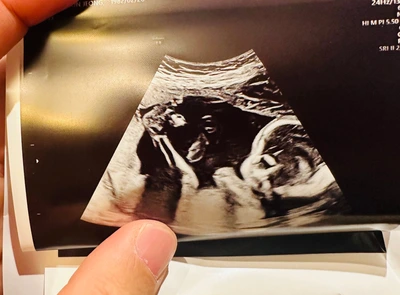

처음이라고 말하기엔 민망할 정도로 병원에 갈 때마다 머리 길이를 재고 다리길이를 재고하며 여름이가 잘 자라고 있다는 걸 확인받지만 이번엔 좀 달랐다.

양수검사, 양수를 통해 아이가 장애인지 혹 염색체의 이상은 없는지 확인한다는 검사를 앞두고 괜히 싱숭생숭해졌다.

다행히도 우리 우려와는 다르게 모든 염색체 정상, 머리 크기 정상, 팔다리 예쁘게 잘 크고 있고 심지어 엄빠한테 잘 보이겠다고 사진 찍는 찰나에 예쁘게 돌아누워주시기까지 했단다.